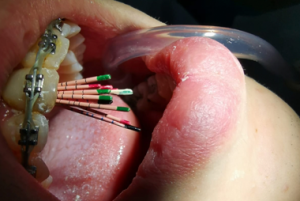

Root canal treatment, cracks and fractures in the teeth, deep decays in the teeth, cleaning, disinfecting and filling the infected tissue in the canals of the tooth with root canal filling materials as a result of the loss of vitality of the nerves and veins in the tooth is called canal treatment.

In cases where the tooth loses its vitality as a result of excessive force on the tooth as a result of orthodontic treatment